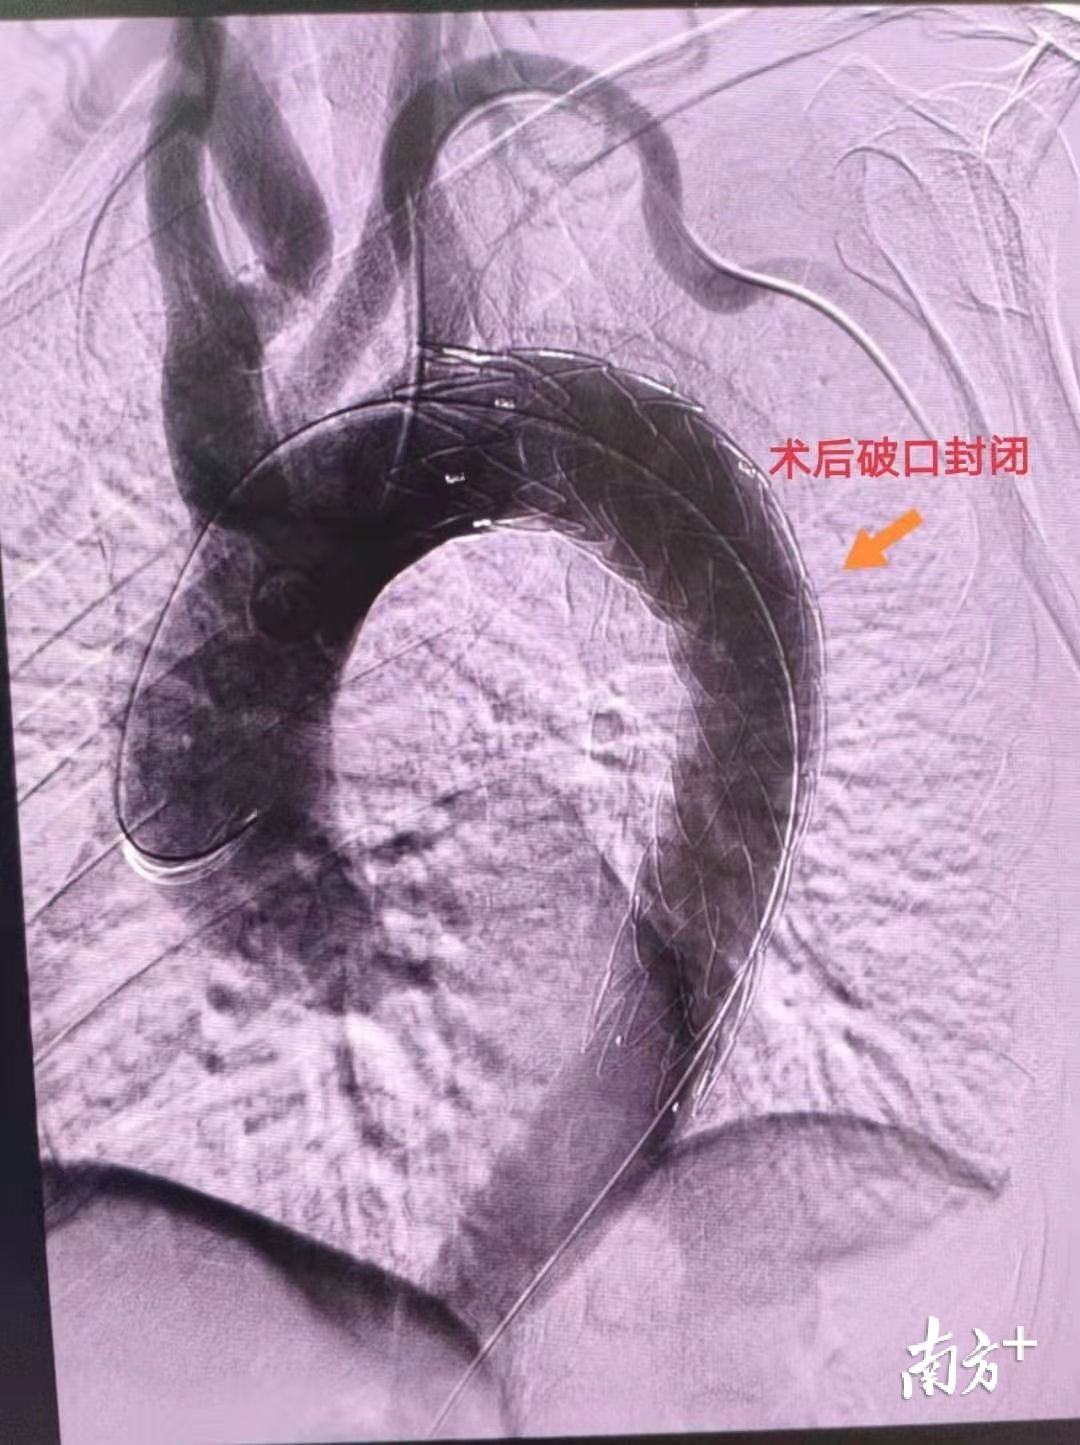

大年初一上午9时 , 手术开始了 。 肖建民带领团队为陈阿伯进行了动脉夹层支架植入手术 。 这是一个微创手术 , 需要从陈阿伯的股动脉穿刺 , 将支架送到血管破口处 , 支架定位后自动膨胀 , 堵住血管破口 。 在全体医护人员和患者的齐心努力下 , 肖建民将支架精准对位 , 夹层完美封堵 , 手术顺利完成 。